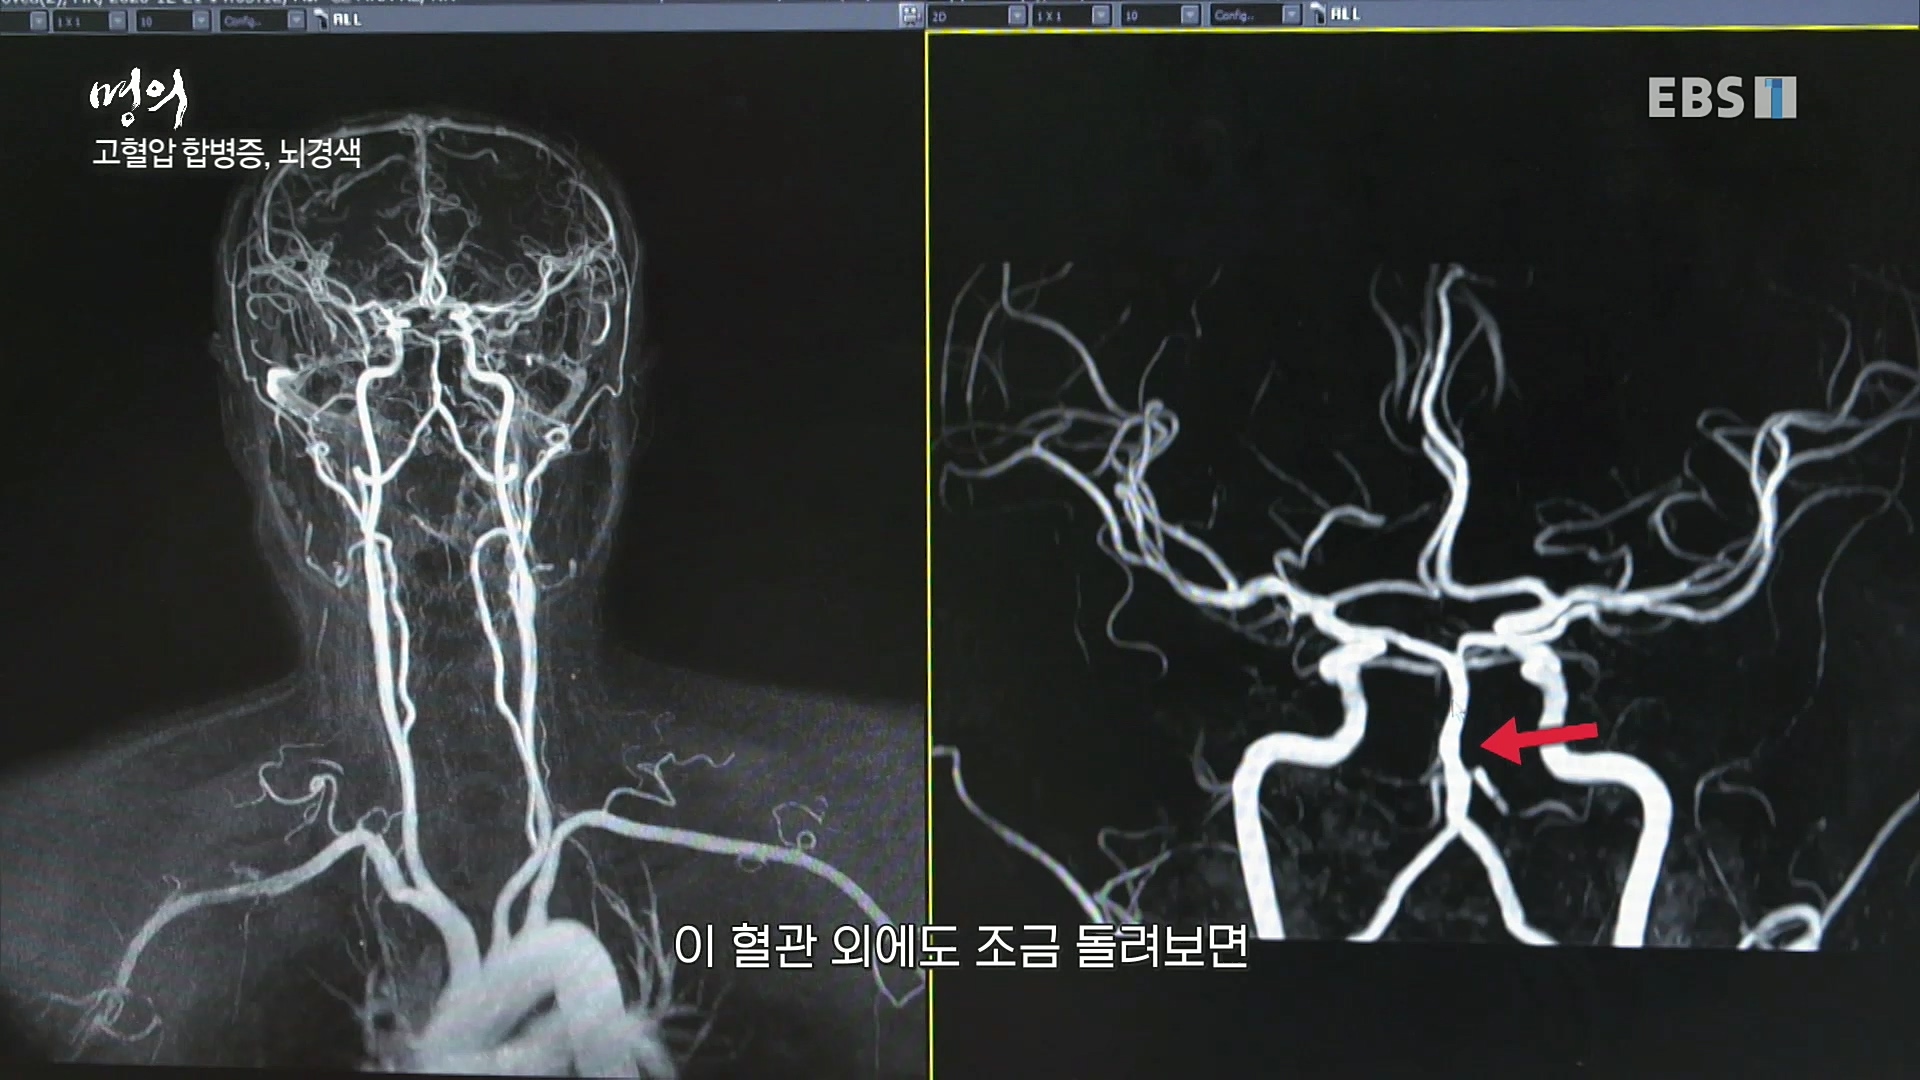

[한국강사신문 정헌희 기자] 오늘 12일(금) 21시 50 EBS1 <명의>에서는 강북삼성병원 순환기내과 성기철 교수의 “아이고, 혈압이야 – 고혈압을 잡자!” ...

이날 고혈압 질환은 순환기내과 전문의 김철호 교수, 권현철 교수, 성기철 교수, 고지혈 질환은 심장내과 전문의 한기훈 교수, 혈관외과 전문의 ...